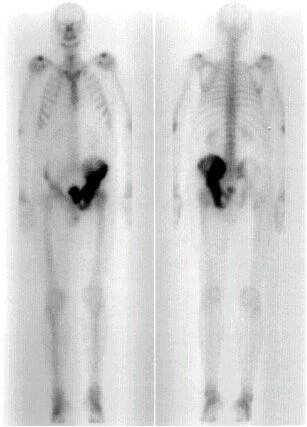

Obr. č. 2: Celotělová scintigrafie skeletu v přední a zadní projekci